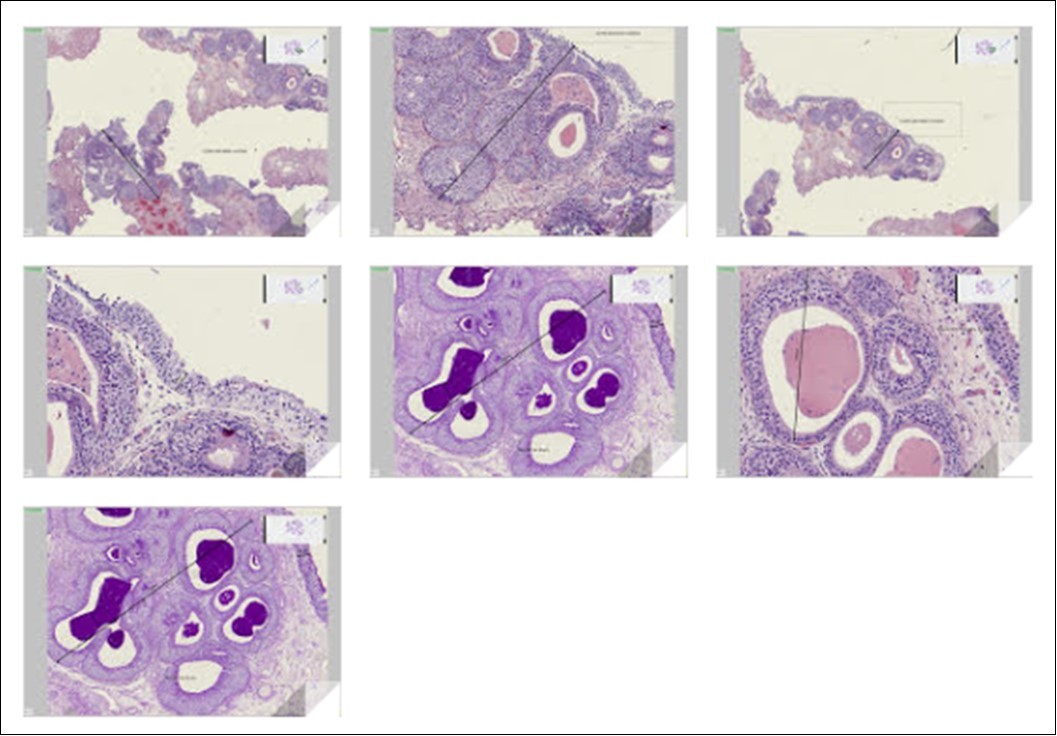

In histology, the samples were included in full. They involved a bladder lining lined with a regular epithelium (Figure 2).

Glandular and cystic cystitis (minor form) with numerous islets of Von Brunn which contain reddish, PAS-positive material. The islets are partly dilated, have grouped and form nodules up to approximately 2 mm in maximum diameter, from which the focal pseudo-tumor appearance results.

It is not histologically a glandular cystitis (major form) with intestinal metaplasia with cylindrical goblet cells and / or Paneth cells. There is no tumor.

In histology, in a first phase, the proliferation of urothelial cells to the chorion, leads to the formation of "nests VON BRUNN". These islets or nests of urothelial cells develop a central light. This light is lined with secreting cells giving rise to the formation of real glandular structures that can take on a pseudo-colonic appearance with the presence of goblet cells. Sometimes, the light from these islets of VON BRUNN extends to form real cysts containing colloid matter. At this stage, the separation between cystic and glandular cystitis is not histologically well defined.

Immunohistochemistry comes to highlight features not visible in simple histology. Chromogranin immunostaining highlights spindle-shaped endocrine cells in the nests of Von Brünn, of glandular cystitis 26 between the epithelial cells and contains intracytoplasmic neuroendocrine granules positive for silver staining of Grimelius.

Ultimately, the histological immune analysis makes it possible to distinguish the frequent pure cystic cystitis, as in our observation, developed from the islets of Von Brunn cyslized with accumulation of mucin, of the glandular form or the unstratified muciparous cells form glands in the superficial chorion without atypia or mitosis 27.